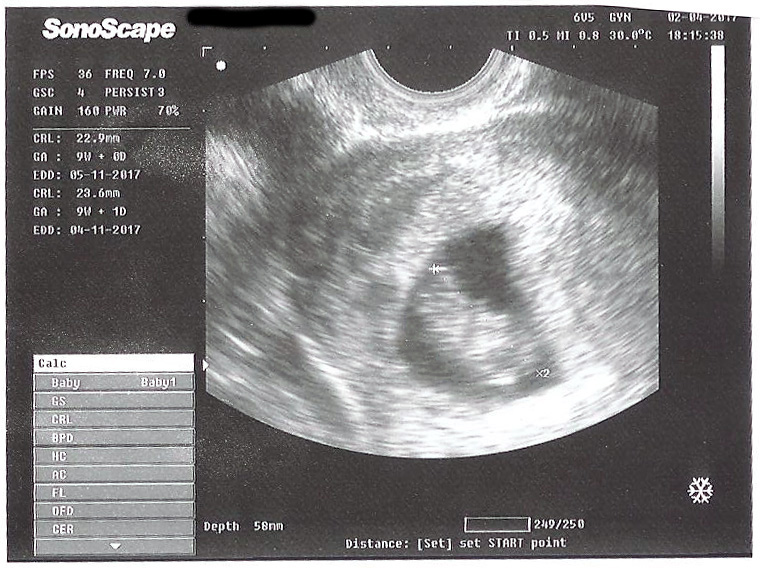

Any predictions based on Ramzi or nub theory? Thanks!

Attachment 35894

Looks like a boy to me :)

Early but boyish [emoji170]